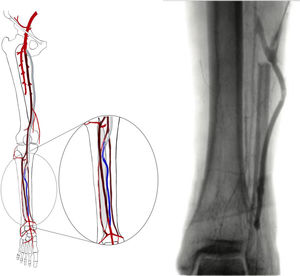

La fase siguiente de la planificación es la angiografía convencional diagnóstica, que realizamos sistemáticamente, excepto en pacientes con enfermedad renal crónica avanzada (depuración de creatinina <30ml/min). La inyección de contraste (80cc, 6ml/s, 600PSI de presión), se realiza mediante una punción femoral retrógrada con introductor 4F. Esta técnica permite el reclutamiento de todos los colaterales responsables de la irrigación de la pierna y del pie, desde la arteria femoral profunda, obteniendo así un gran detalle anatómico (fig. 2).

La calidad de la angiografía es crucial para la planificación de cualquier revascularización distal o ultradistal, con imágenes en 2 proyecciones y tiempos de exposición prolongados que permitan visualizar las arterias del pie. Los tiempos de exposición pueden alcanzar los 60s y, como tal, nos parece esencial la realización/supervisión de este examen por parte de un miembro del equipo con experiencia en este tipo de revascularización, con el fin de optimizar el uso de la radiación y disminuir la cantidad de contraste. En pacientes con contraindicación para la angiografía, se realiza la planificación basada exclusivamente en los hallazgos del eco-Doppler.

Con los datos de la angiografía diagnóstica podemos elegir las arterias capaces de proporcionar flujo directo a un pie con lesiones tróficas y decidir si el paciente es un buen candidato a un procedimiento endovascular o convencional.